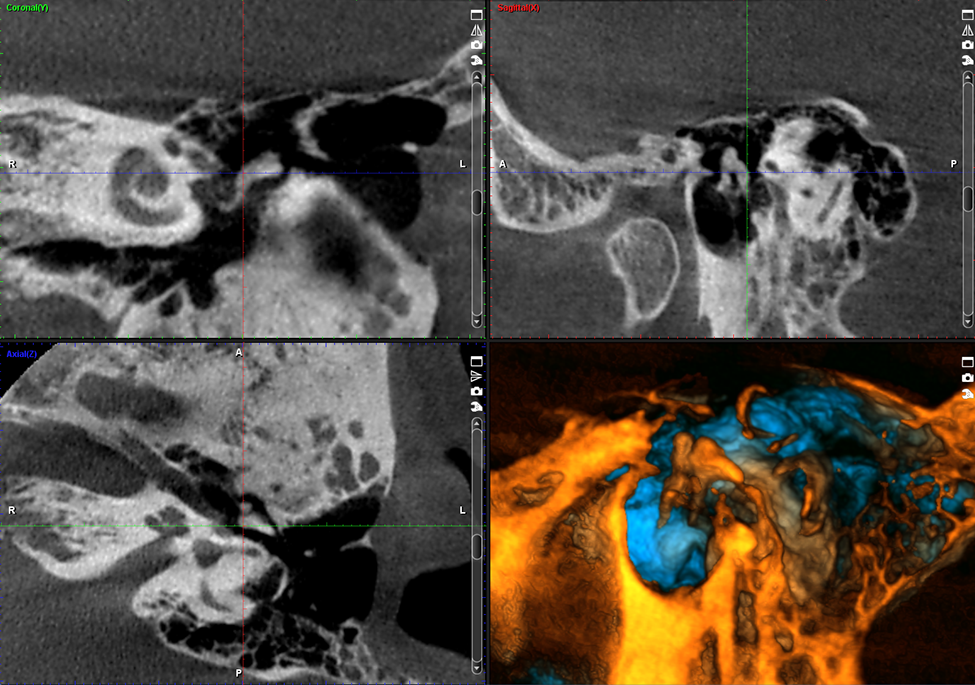

Ustawienia wstępne dla obrazowania TMJ

Planmeca ProMax 3D Mid jest nie tylko doskonałym wyborem w przypadku obrazowania stomatologicznego, ale również świetnie sprawdza się w przypadku pełnego obrazowania twarzowo-szczękowego. Unit posiada wiele ustawień wstępnych dla poszczególnych obszarów anatomicznych opracowanych specjalnie z myślą o obrazowania uszu, nosa i gardła.

Obrazy Kliniczne Planmeca ProMax 3D Mid